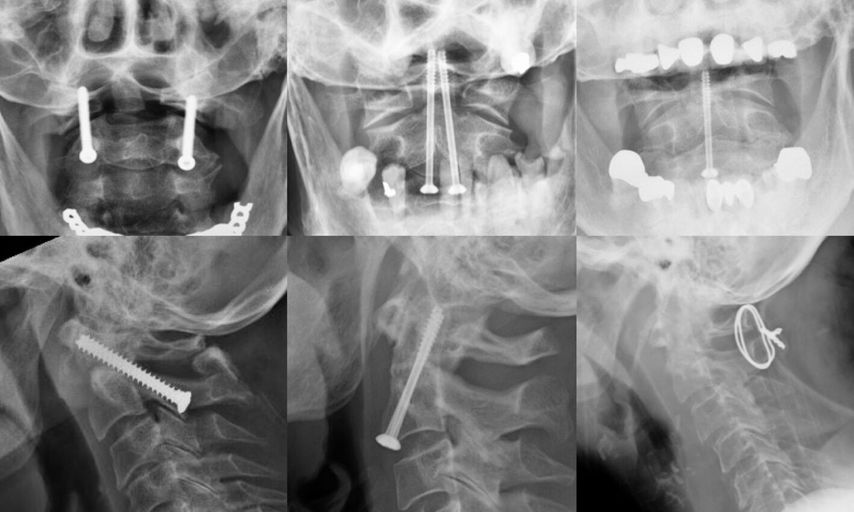

Außerdem bringt eine straffe Pseudoarthrose nach Typ-II-Fraktur keine vermehrten Schmerzen oder funktionellen Einschränkungen mit sich. Weder im NDI noch in der mRS oder der „Smiley Webster Pain Scale“ (SWPS) zeigt sich ein Unterschied zwischen straffer Pseudoarthrose und knöchern durchbauter Densfraktur.5 Eine straffe Pseudoarthrose kann ebenso wie eine knöcherne Durchbauung eine ausreichende Stabilität erzielen, was gut mit einer Funktionsaufnahme im CT überprüft werden kann (Abb. 3).5

Abb. 3: Röntgen einer straffen Pseudoarthrose: Reklination (links) und Inklination (rechts)